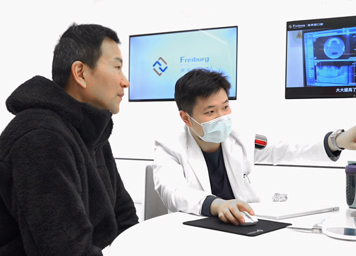

可视舒眠种植牙全球首发技术革新 让种牙看得见,打破常规 更安全·更精准